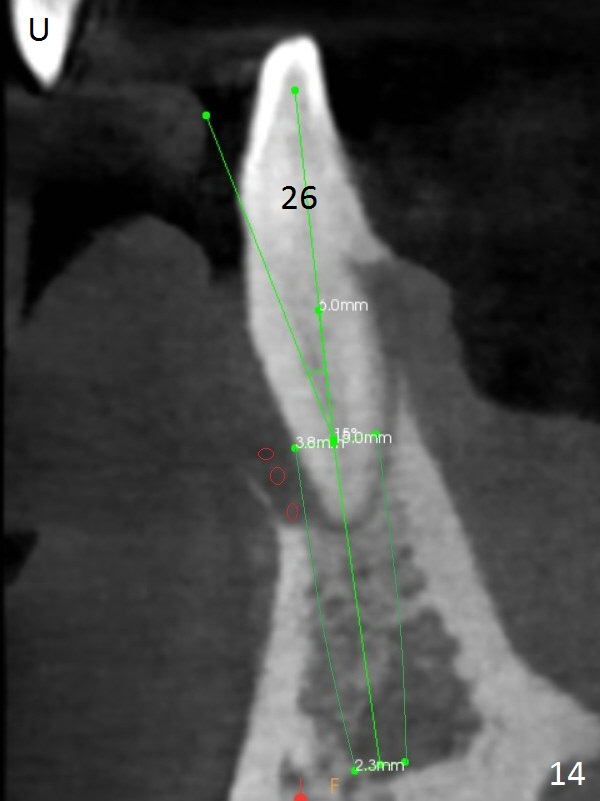

Class II Division II malocclusion (Fig.2,6) will make it difficult to restore #23-26 implant-supported FPD. Although the teeth #7-10 may need to be replaced later (Fig.7,8), enameloplasty will be conducted for #7-10 (Fig.9 white area; Fig.12 black circles (gross reduction)) prior to #23-26 extraction and implant placement (Fig.10). To be flexible in restoration (angulation) and possible future hybrid denture, 2-piece narrow implants will be placed (3.0 or 3.3 mm) instead of 1-piece ones. In fact CBCT shows that the narrowest regular implant (3.8 mm) can be placed in the lower anterior region (Fig.13-15).